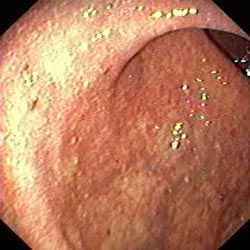

Толстая кишка в норме Умеренное воспаление язвенного колита